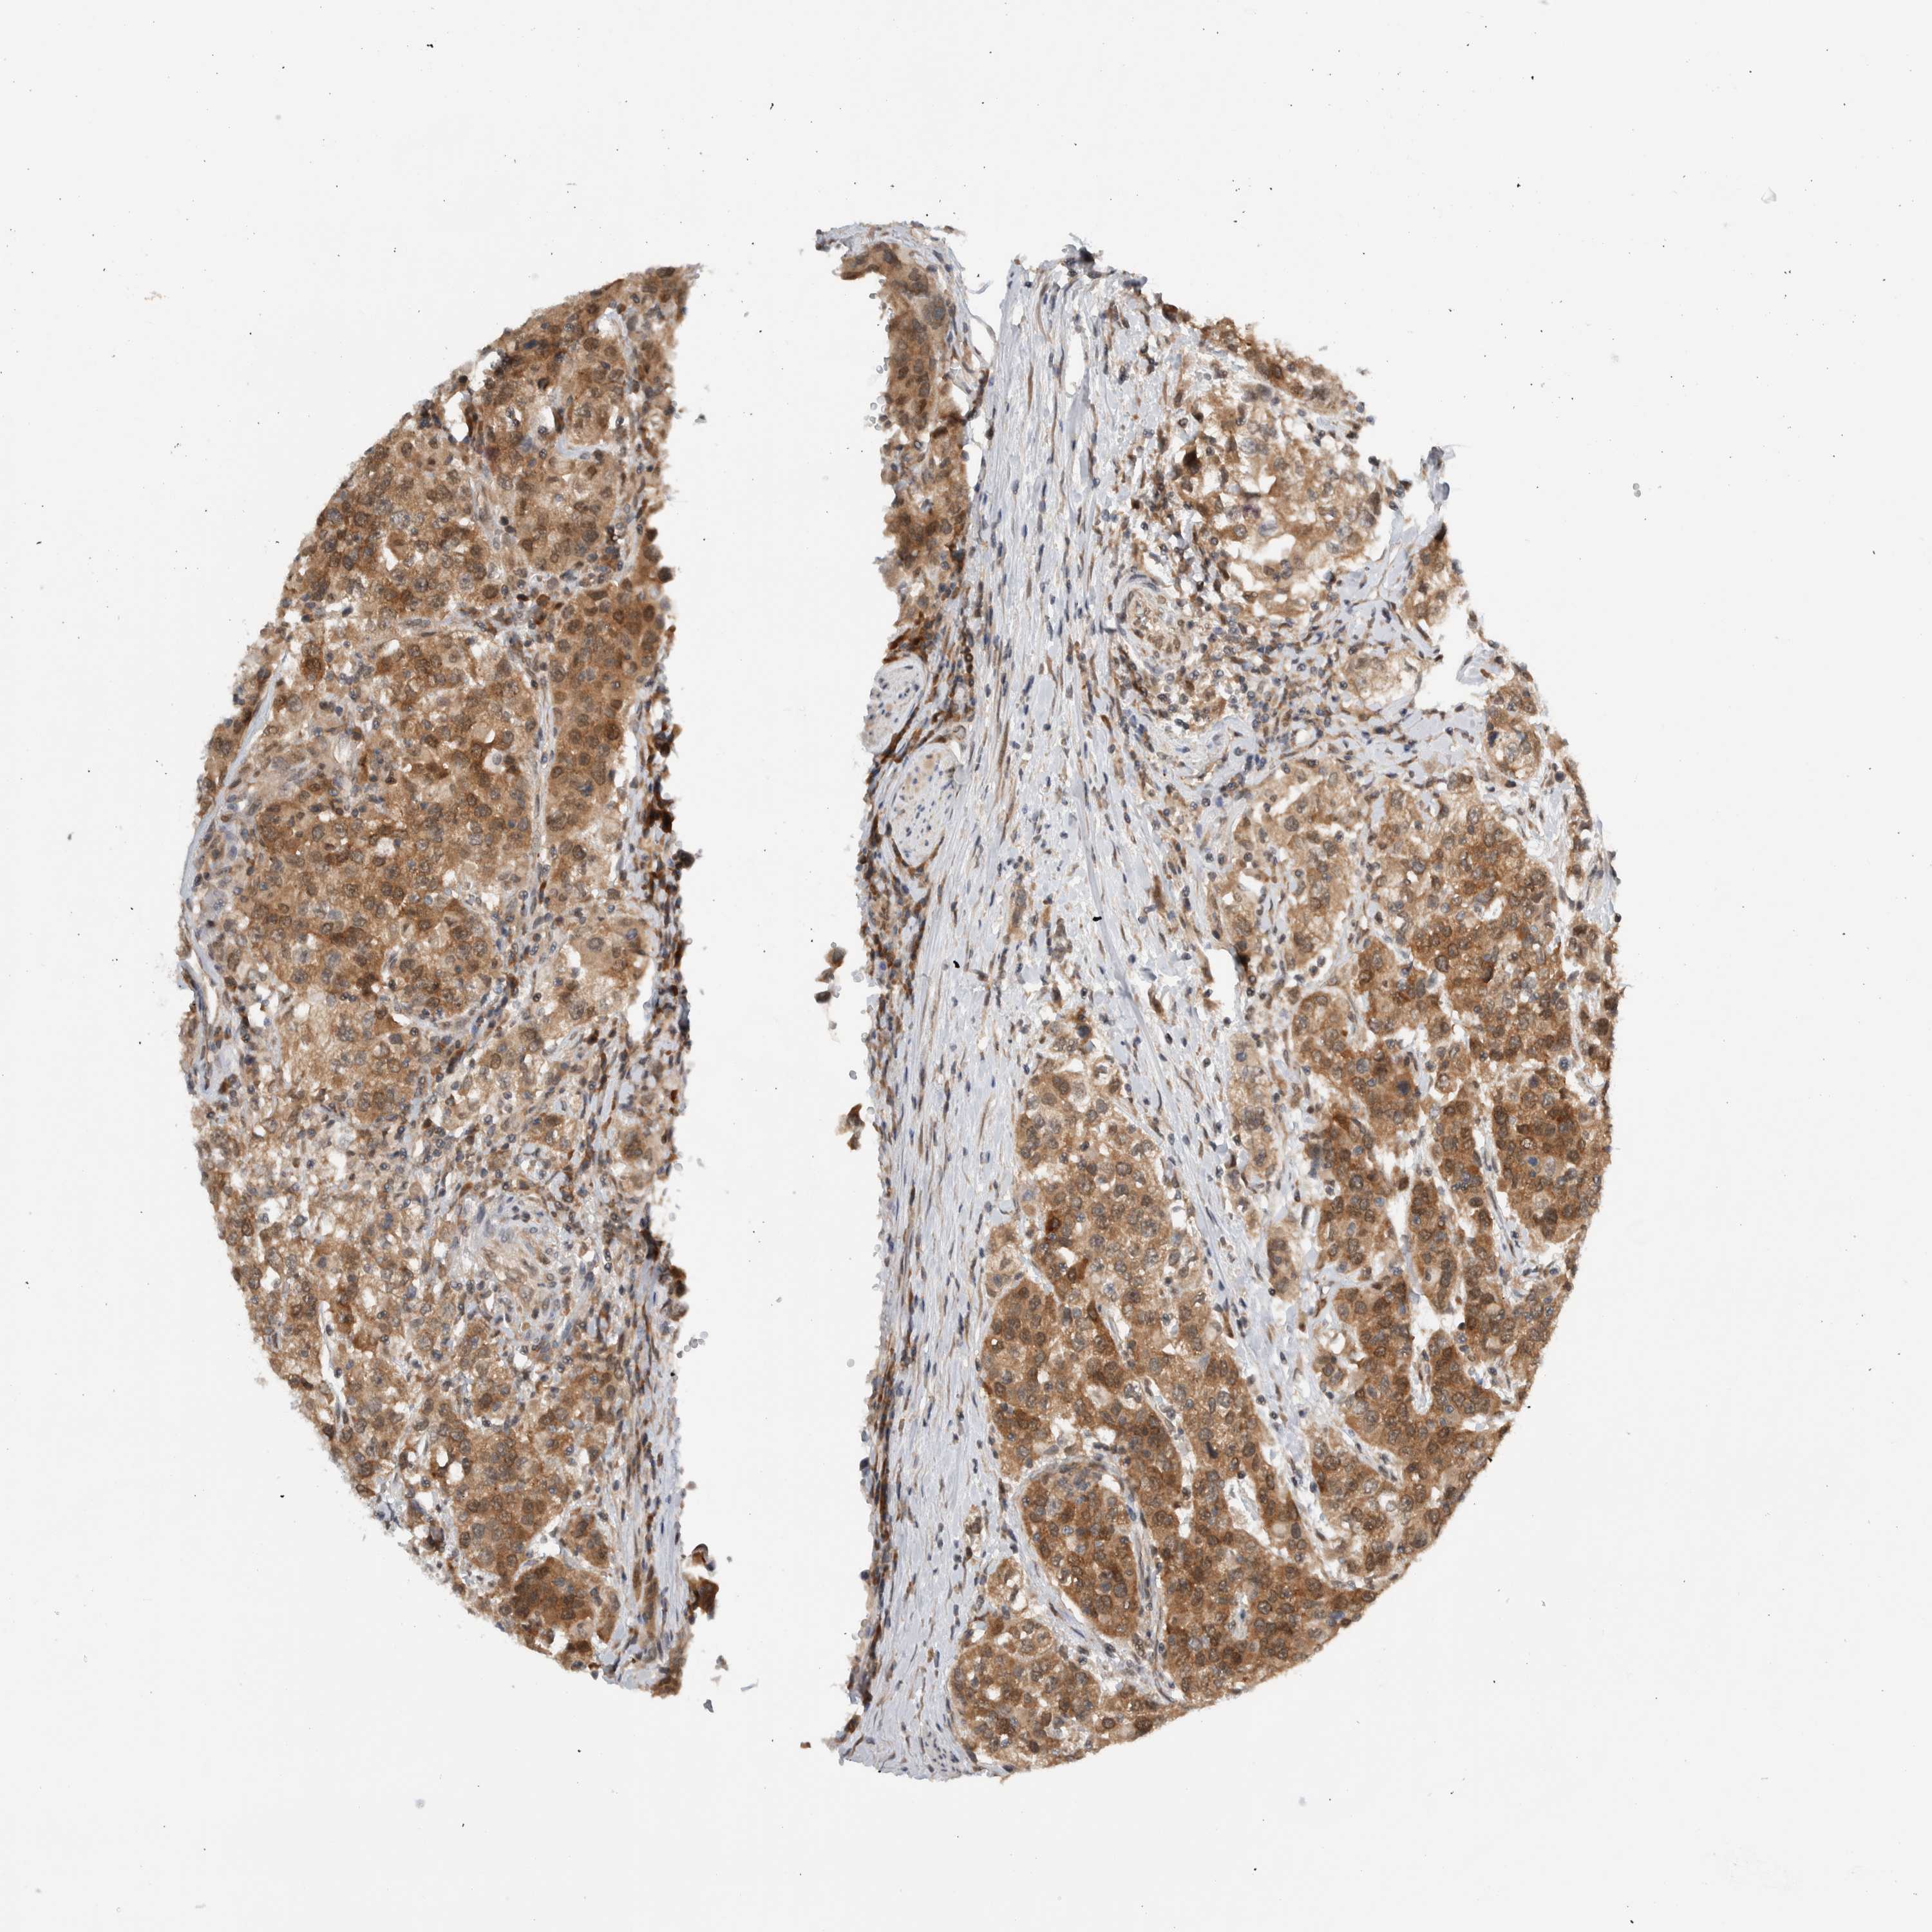

UROTHELIAL CANCER - Protein expressioni

A mouse-over function shows sample information and annotation data. Click on an image to view it in a full screen mode. Samples can be filtered based on level of antibody staining by selecting one or several of the following categories: high, medium, low and not detected. The assay and annotation is described here.

Note that samples used for immunohistochemistry by the Human Protein Atlas do not correspond to samples in the TCGA dataset.

Antibody stainingi

Antibody staining in the annotated cell types in the current human tissue is reported as not detected, low, medium, or high, based on conventional immunohistochemistry profiling in selected tissues. This score is based on the combination of the staining intensity and fraction of stained cells.

Each image is clickable and will lead to virtual microscopy that enables deeper exploration of all samples and also displays staining intensity scores, fraction scores and subcellular localization as well as patient and tissue information for each sample.

Antibody HPA023078

Antibody HPA023391

Urothelial carcinoma, High grade